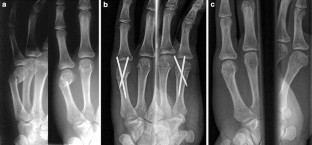

Fig. 1

Fig. 2